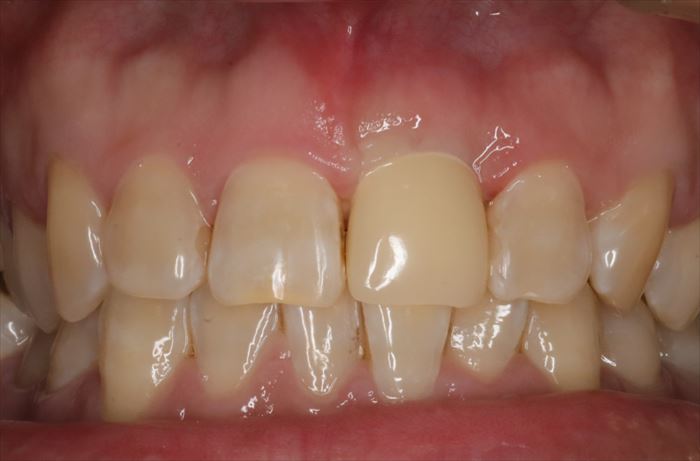

初診時の状態です。